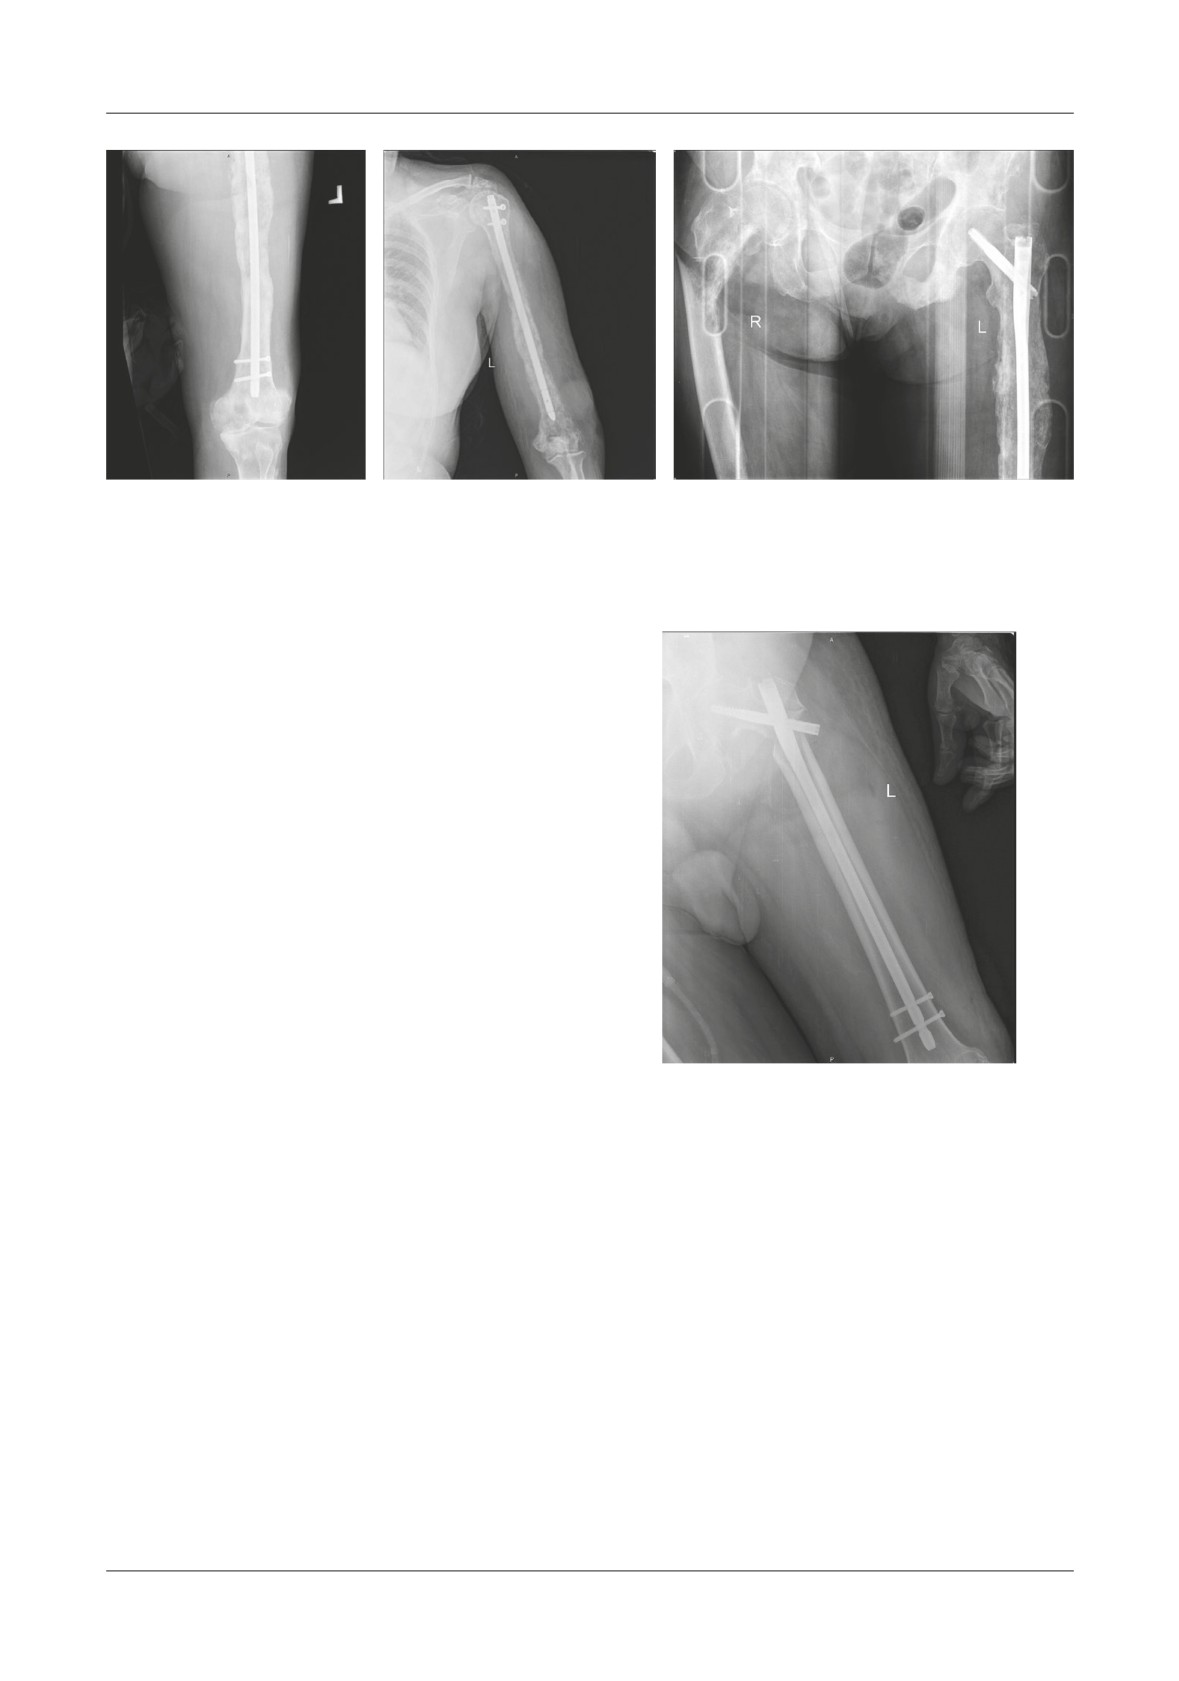

Figure 2. A,B. Axial CT images that reveal the lytic bone area from within the femoral neck as well as the zone

of the pathologic fracture. C. Coronal CT reconstruction shows the tumor mass that expands the muscles

surrounding the proximal femoral area. D. 3D CT reconstruction meant to carefully show if there are any

other fractures that expand distally. E. AP X-ray of the right coxo-femural joint

A

B

Figure 3. A. AP X-ray of the coxo-femural joint which shows loosening of the cervico-cephalic

nail. B. AP X-ray of the distal femur that shows both of the distal screws being broken.

Figure 4. A. Te first pathologic fracture occurred in the sub trochanteric area and it was stabilized with a long gamma nail.

B. After 8 months the patient presents at the hospital with pain in the left arm - a humeral shaft fracture is depicted on x-rays

and intramedullary nailing is done to the humerus. C. After another 10 months the patients suffers a sub trochanteric fracture

to the contralateral femur

Figure 5. Te result of our surgery can be seen

fracture is depicted on x-rays and intramedullary nailing

on this AP X-ray of the patient’s left hip